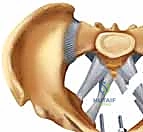

4. الرد المفتوح (Open Reduction)

بعد تنظيف المفصل من أي أنسجة متمزقة أو جلطات دموية، يتم استخدام ملاقط عظمية خاصة (Pelvic Reduction Forceps) لجذب عظام العانة المنفصلة وإعادتها إلى موضعها التشريحي الصحيح بدقة مليمترية.

5. التثبيت الداخلي (Internal Fixation)

بمجرد استعادة الوضع الصحيح للعظام، يقوم الدكتور هطيف بتثبيتها باستخدام صفيحة معدنية متخصصة (غالباً صفيحة إعادة بناء متعددة الثقوب مصنوعة من التيتانيوم أو الفولاذ المقاوم للصدأ الطبي). يتم تثبيت هذه الصفيحة عبر المفصل العاني باستخدام مسامير قشرية (Cortical Screws) تُغرس بعمق في عظام العانة الصلبة لضمان تثبيت قوي يتحمل ضغط الجسم.